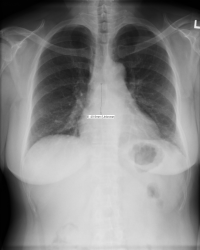

Figure - 19

How to draw the Sweet Spot™ |